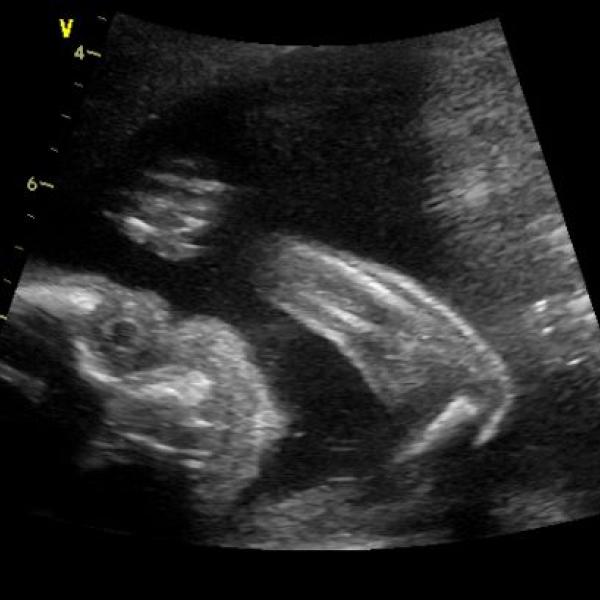

:°~°: táák huráááá, druhý UTZ za mnou.

Mimi naprosto úžasné, zdravé, krásné, v pořádku a je to dle tušení chlapeček..

takže budu mít malého motorkáře.